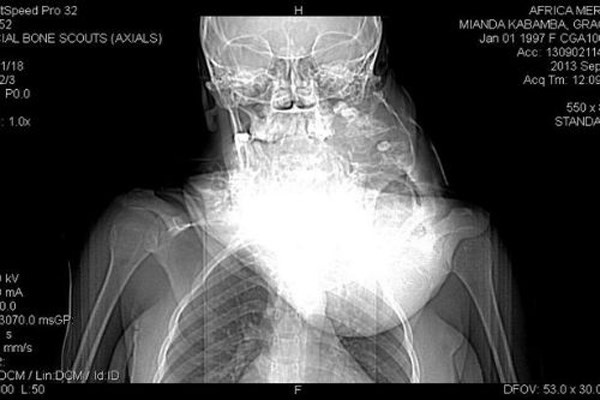

| Cậu bé 12 tuổi Chia Jun sống tại Trung Quốc, tranh thủ giờ ra chơi đã chạy ra căng tin của trường mua 1 hộp mỳ ăn liền. Không may, chiếc xe máy điện của 1 phụ huynh trong lớp đi trên sân trường đã lao đến đâm ngã cậu bé làm đôi đũa chọc thẳng vào họng của Chia. các ảnh chụp X quang cho thấy, đôi đũa tuy xuyên thủng sâu vào cổ họng cậu bé nhưng lại không gây ra nguy hiểm gì đến tính mạng của Chia Jun. |